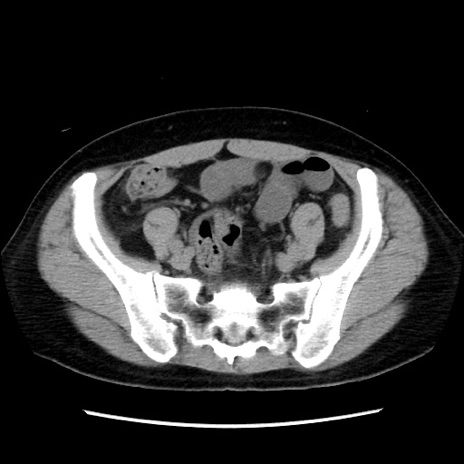

症例10(横断像)

【症例】 50歳代女性

【主訴】 腹痛

【現病歴】前日生レバーを食べた。今朝に排便あり。 昼前に突然発症の腹痛を生じ、当院救急外来を受診した。

【既往歴】 子宮筋腫にてで子宮全摘後

【身体所見】 意識清明、腹部:平坦、軟、下腹部やや左を中心に圧痛・反跳痛あり、筋性防御あり

【データ】WBC 7800、CRP 0.07